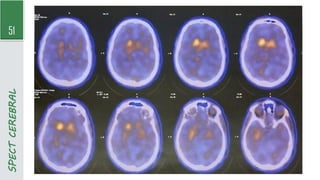

TC por emissão de fóton único (SPECT) com traçador de dopamina (DaT Scan)

- Exame de neuroimagem funcional que mostra a concentração de radiofármaco em neurônios nigroestriatais

- ↓Captação não é específico da DP (mais exame normal inviabilizada diagnóstico de DP)

SPECT

CEREBRAL